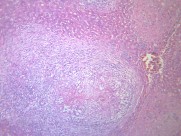

虫卵肉芽肿(12)张

虫卵肉芽肿:虫卵是血吸虫病的主要致病因子。虫卵主要沉着在宿主的肝以及结肠肠壁等部位,所引起的虫卵肉芽肿以及之后的纤维化是血吸虫病的主要病变。